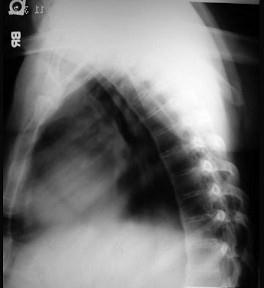

问题 男,21岁,下腰不适,晨起加重半年余,X线检查如图,请选出最可能的诊断 ( )

选项 A、化脓性脊柱炎 B、阻滞椎 C、脊椎退行性变 D、强直性脊柱炎 E、类风湿关节炎

答案 D